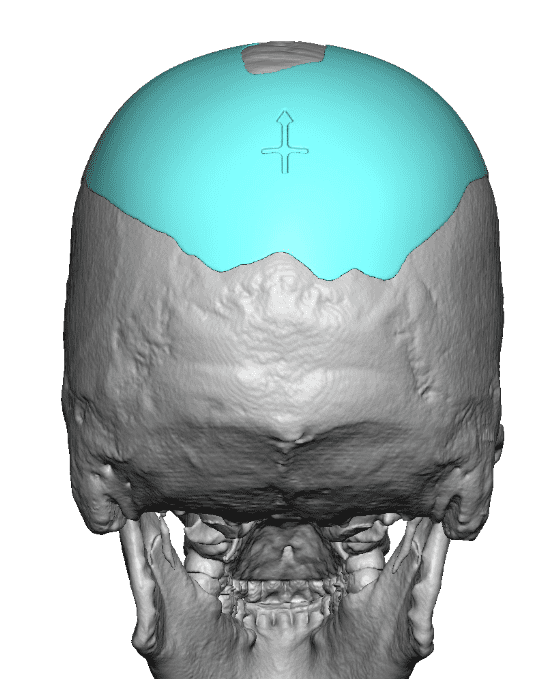

Desire for a higher and more prominent crown of the skull.

Crown of skull augmentation using a custom skull implant.

Desire for a higher and more prominent crown of the skull.

Crown of skull augmentation using a custom skull implant.